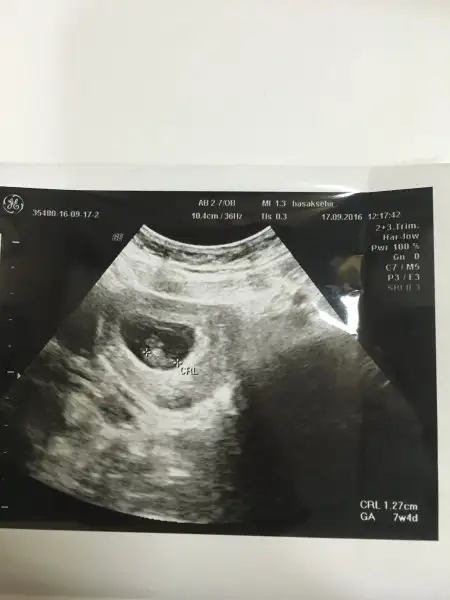

kizlar ultrasonda gordugumuz 7 haftalik bebis hala bir noktacik... internetten bakiyorum cogu cenin seklinde en azindan kafa govde belli sizinkiler nasil benimki cok mu kucuk ölçüm yapmamis ultrason makinesi cok telasliyim

Can'ım ben öğlen gittim 7+4 benimde boyle

Canım içinde bir noktacık zaten derinden gözüküyo sonuçta içimizde :) intten baktıkların yakınlaştırılmış bilgisayar ortamında kimse o fotolardaki kadar net göremiyo bnde yeni çektrdm hiç bişey anlaşılmıyo resimlerdeki gibi olmasını brkleme :)